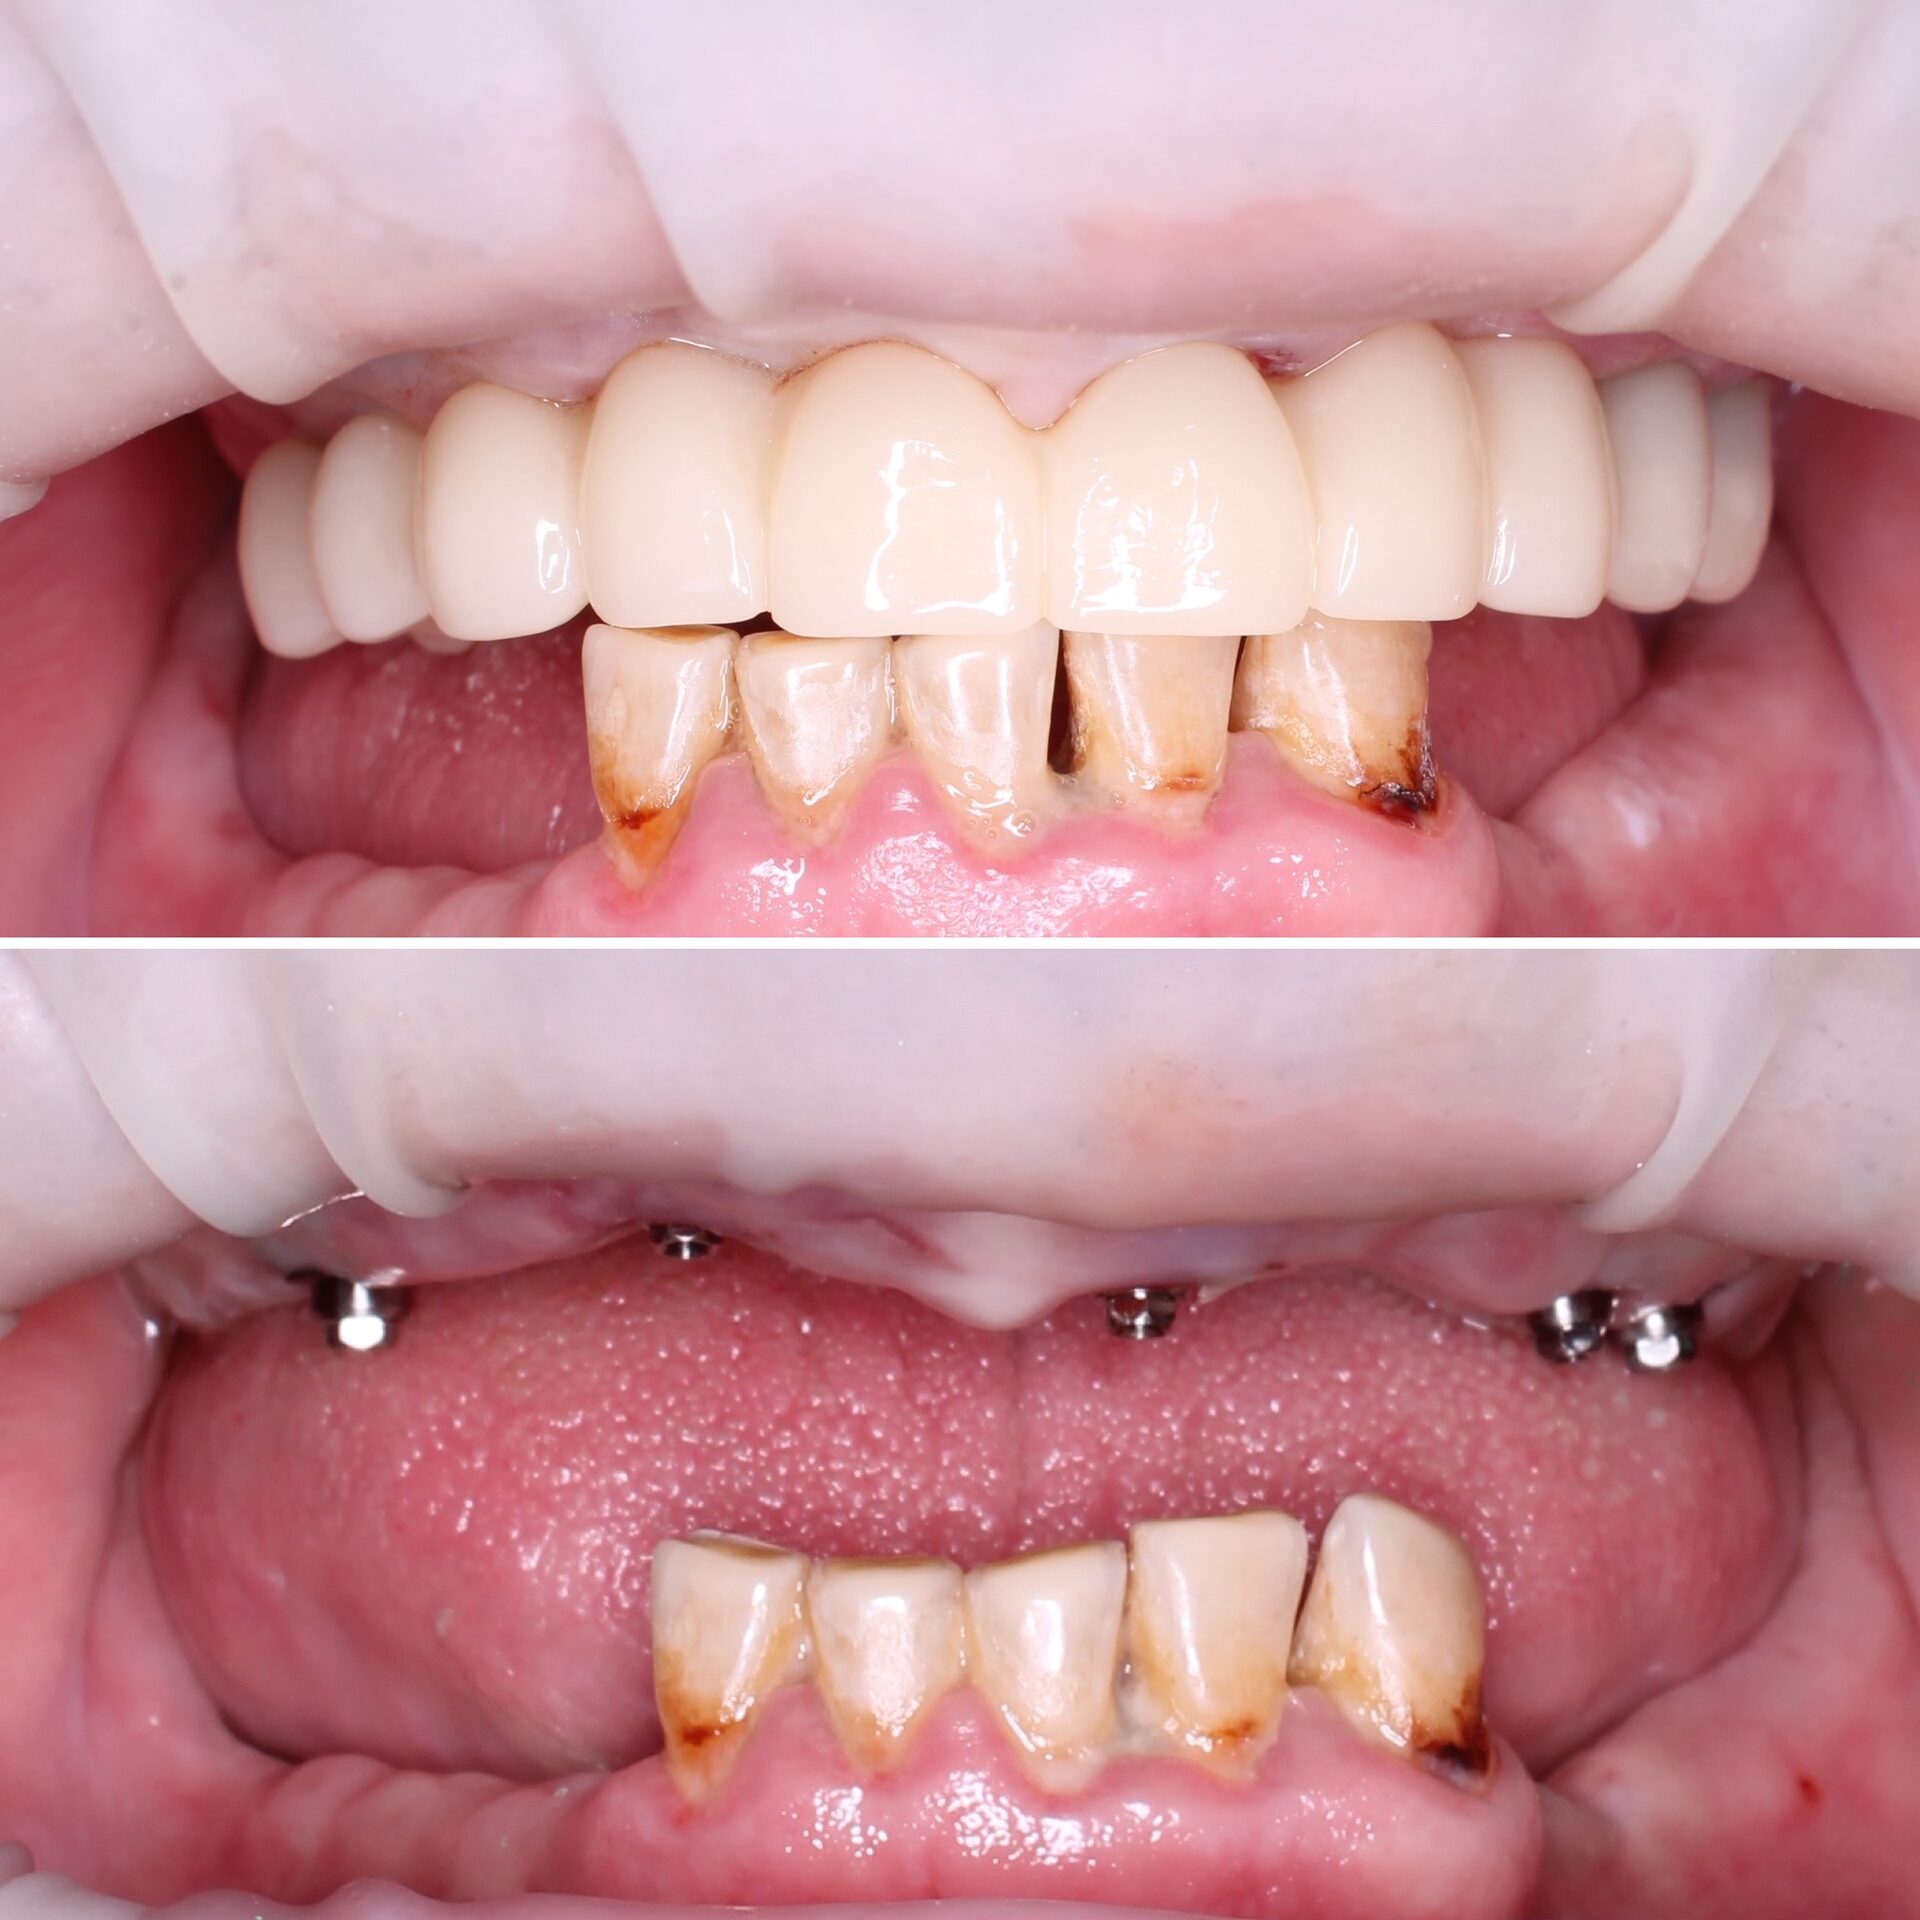

ALL-ON-X